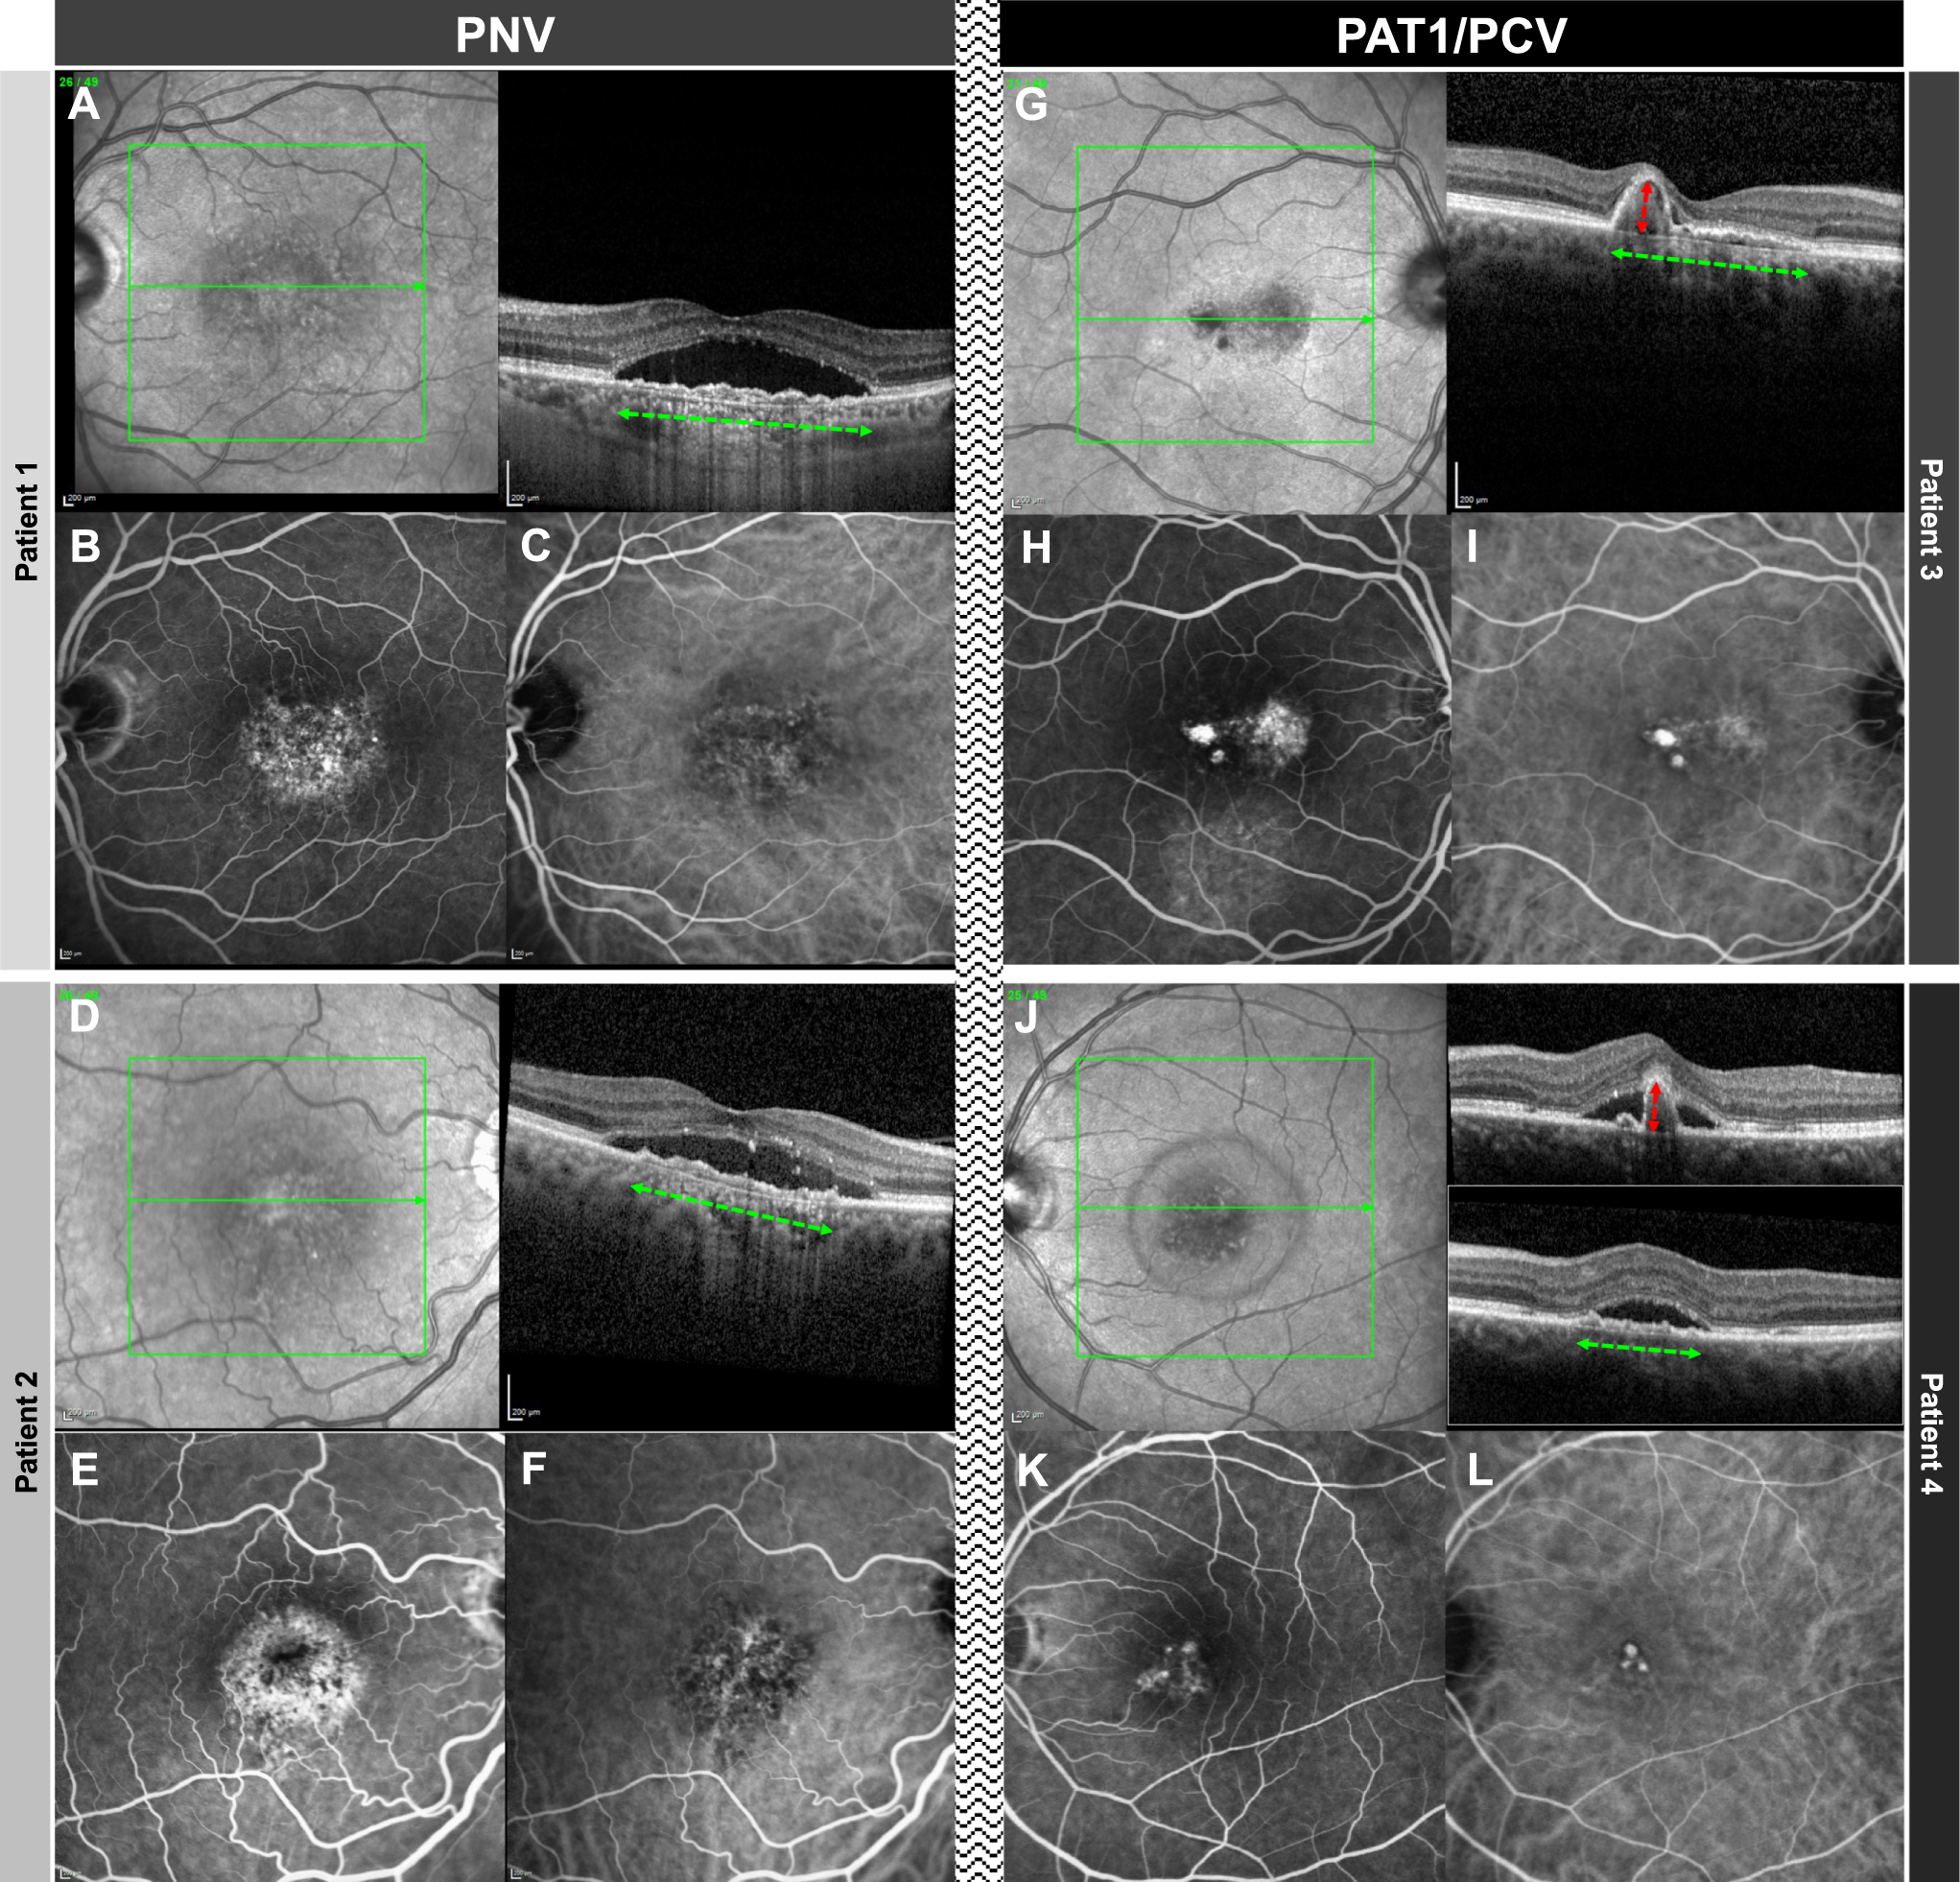

Fig. 1: Comparison of two cases PNV and two cases of PAT1/PCV.

In patients 1 and 2 with PNV, OCT (A + D) demonstrates a flat irregular PED (alternatively double layer sign) and subretinal fluid. Note that the flat irregular PED has a wide horizontal diameter (green horizontal arrow) and low height. Whereas FA (B + E) shows unspecific hyperfluorescence, ICG (C + F) shows a type 1 choroidal neovascularization without evidence of aneurysmal/polypoidal lesions. In patients 3 and 4 with PAT1/PCV, OCT (G + J) shows a peaking PED (red vertical arrow) with greater height having an adjacent double layer sign (diameter demonstrated with a green horizontal arrow). FA (H + K) shows a more focal hyperfluorescence, and ICG (I + L) clearly demonstrates the presence of aneurysms/polyps.